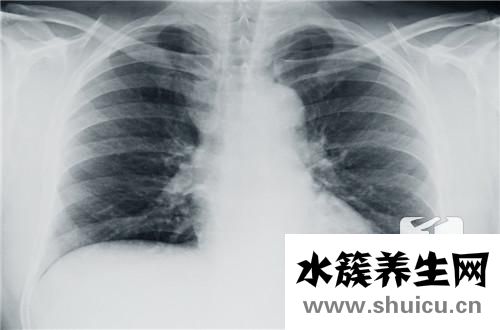

眾所周知,我們的胸腔總面積為一定的空白頁,而普通氣胸是指通過胸膜進入胸腔而引起擠壓的蒸汽。 氣胸屬于肺部疾病。 大多一些年輕人在男人中更常見。 根據胸腔鏡手術,可以減少蒸氣。 可是 盡管我不知道實際的術后復發多少錢,可是它手術治療的復發率很高,因此有很多癲癇發作原因應引起重視。

氣胸發作與治療方式相關。一般而言,單純性抽真空的保守治療者復發較高;選用胸腔引流管行閉式引流者,因為胸膜反應和胸膜粘連復發會有一定的減少,可是也會產生紊亂黏連的嚴重危害,可能引起更加難除的發作。醫師一般建議選用肺葉切除術微創手術醫治。肺葉切除術微創手術能夠完全摘除肺大皰,進而除根氣胸,使氣胸的復發減少到百分之一下列。使氣胸病人此后始終的道別氣胸發作,再次過上開心、健康的生活。

別稱難治性氣胸。它就是指肺臟基本X線檢查無法發覺顯著變病的身心健康者所產生的氣胸,多見于于年輕人,非常是男士高挑者。依據國外文獻報導,這類氣胸占自發性氣胸第一位,而中國則以繼發性氣胸主導。

其造成體制是在別的肺部疾病的基本上,產生肺大皰或立即損害胸膜增厚引發。常以漫性阻塞性肺氣腫肺氣腫或發炎后化學纖維疾?。ㄈ缥巍⒙苑谓Y核、局灶性肺間質纖維化工藝、囊性肺纖維化等)的基本上,細支氣管炎癥狹小、歪曲,造成活瓣體制而產生肺大皰。腫脹的氣腫泡因營養成分、循環系統阻礙而退行性病變性。

氣胸發病時患者均有呼吸不暢,其比較嚴重水平與發病的全過程、肺被縮小的水平和原來的肺功能檢查情況相關。在年青的吸氣作用一切正常的患者,可無顯著的呼吸不暢,即便肺被縮小》80%,亦僅能在活動時稍感胸悶氣短,而在身患漫性阻塞性肺氣腫肺氣腫的老年康復人,肺被輕微縮小就會有顯著的呼吸不暢。亞急性發病的氣胸,病癥可能更顯著,而漫性發病的氣胸,健側肺部能夠代償性澎漲,臨床表現可能會比較輕。